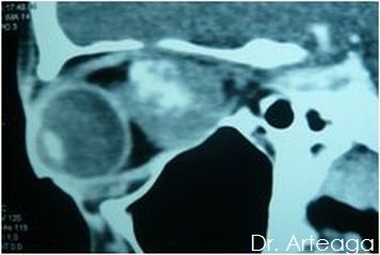

Galería de Imágenes